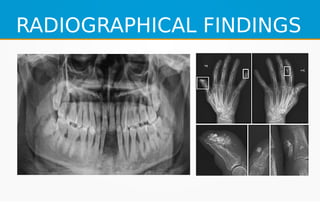

RADIOGRAPHICAL FINDINGS

Classic dental radiographic findings such as extreme widening

●

bilaterally), Partial or complete resorption of condyles and/or

the soft tissues around the jaws.